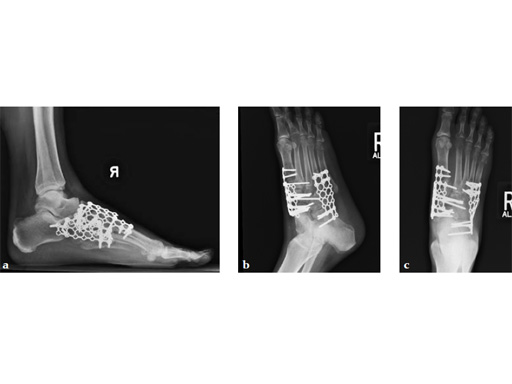

Case 6: VA -locking mesh plate

A 46-year-old female pedestrian was run over. Her foot was crushed by a car. It was a closed injury. She had no other bodily injuries and no medical problems. She sustained massive swelling and shear dorsal soft-tissue injury.

Case provided by Andrew Sands, New York, New York, USA